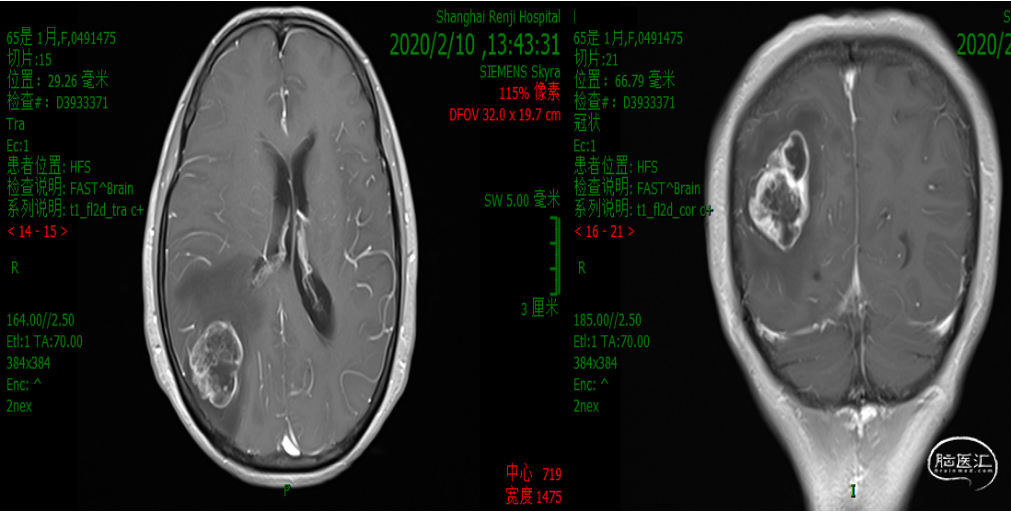

诊疗经过